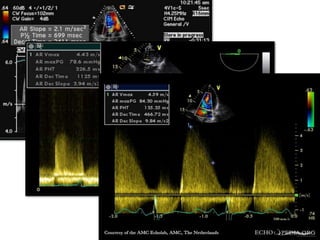

Slope of AR ,PHT

• The deceleration of jet velocity can be described as either

the slope or the pressure half time of the jet.

• A pressure half time less than 250 msec or a slope

greater than 400cm/sec2 is an indicator of severe AR.

Slope(cm/sec2) PHT(msec) DT (msec)

Mild <250 >500 >1800

Moderate 250-400 250-500 800-1800

Severe >400 <250(200) <800

Labovitz et al compared both PHT and the slope with the gold standard angiography,

and found that slope correlated well with angiographic findings than PHT .

Circulation 1983:68:229.